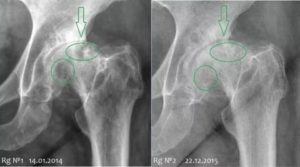

Рентгенография .Наличие очагов остеосклероза, кистовидных просветлений головки характерно для поздних стадий асептического некроза головки бедренной кости. Рентгенологическая картина ранних стадий АНГБК малоинформативна.

Наиболее частой ошибкой является прекращение диагностического поиска после отсутствия, каких либо изменений на рентгенограммах В этих случаях. обязательным методом обследования является МРТ.